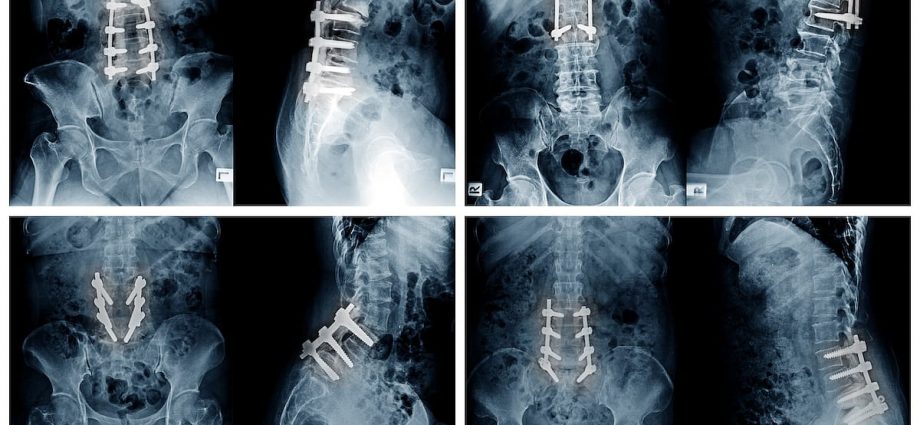

For the study, researchers compared 185 cases performed by three orthopedic surgeons, using X-rays and CT scans to assess screw placement and anatomical differences between male and female patients.

Results showed that the narrower pelvis in men causes rods to angle inward, rather than the parallel alignment that’s preferred.

Men have a narrower pelvis, which means that screws and rods need to be placed differently for them than in women.

Specifically, it’s harder to connect screws to rods in a straight line in men, leading to additional rod bending or other adjustments during surgery, researchers said.